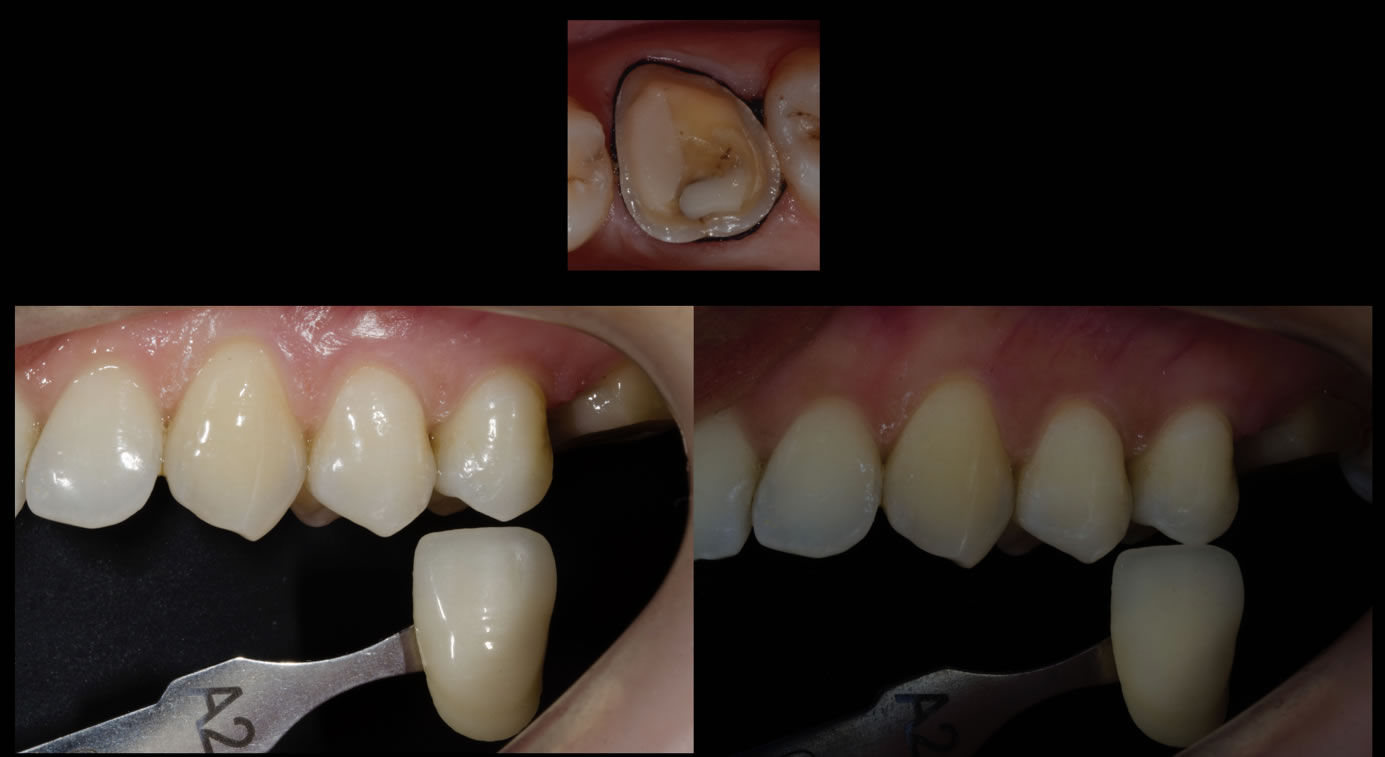

Cas clinique N°1 : Couronne Emax stratifiée sur 26